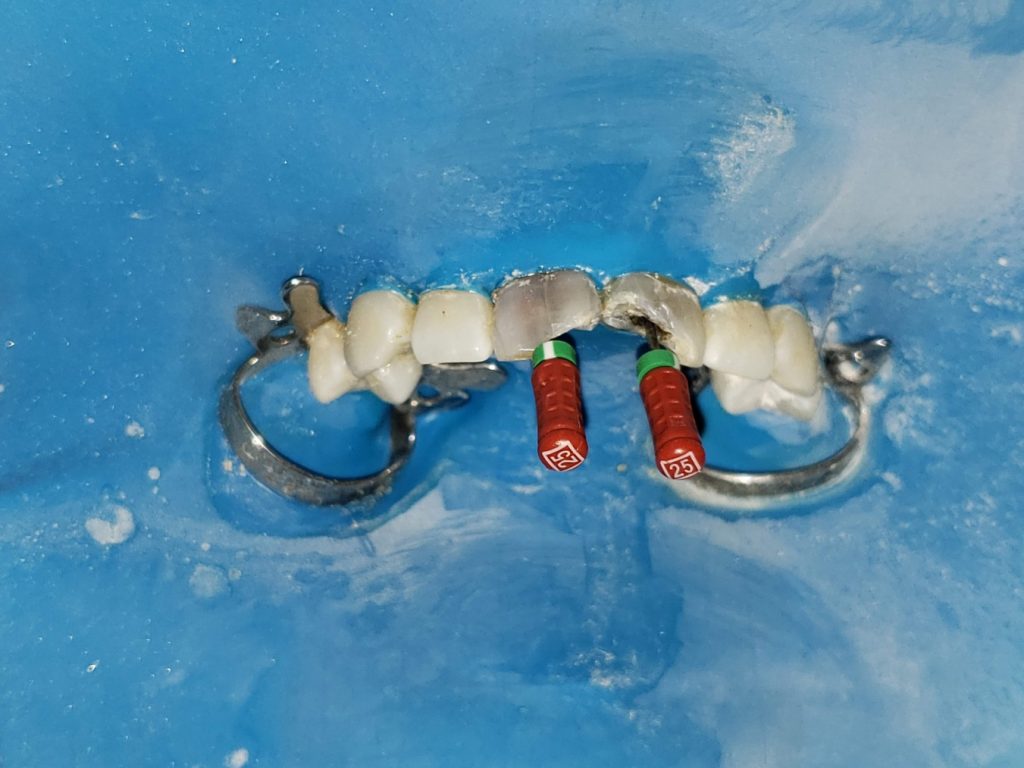

Una vez retirados los tornillos, se irrigó con hipoclorito de sodio al 2.5%, observándose salida de detritos oscuros y olor fétido. Luego, se empleó una lima K #10 25mm (Dentsply-Maillefer) (Fig. 8) como instrumento de exploración y pasaje. Esta lima permite determinar la permeabilidad, establecer la longitud de trabajo inicial y detectar posibles obstáculos o irregularidades en el trayecto del conducto (Cunha et al., 2020). Su uso es indispensable para preparar el camino para la instrumentación sin generar bloqueos ni desvíos. Se realiza la conductometría con limas K 25 de 25mm de largo Dentsply-Maillefer (Fig 9-10).

Conometría y verificación de la longitud de trabajo

Una vez finalizada la instrumentación escalonada, se procedió a realizar la conometría (Fig 14-15) utilizando conos taper 06 calibre 35 (Meta-Biomed), con las que se había logrado una leve resistencia en los tercios medio y apical. Esta elección permitió confirmar la longitud de trabajo de manera efectiva y predecir la adaptación de los conos de obturación. Se obtuvo una radiografía periapical de control con las limas posicionadas en los conductos (fig 10), la cual confirmó la coincidencia con la longitud previamente estimada (23 mm). También se registró la fotografía clínica correspondiente, evidenciando la locali- zación precisa de los conos dentro de los conductos (Fig. 9)

Fig. 9 Foto conductometría limas K 25

Fig. 10 Rx Conductometría